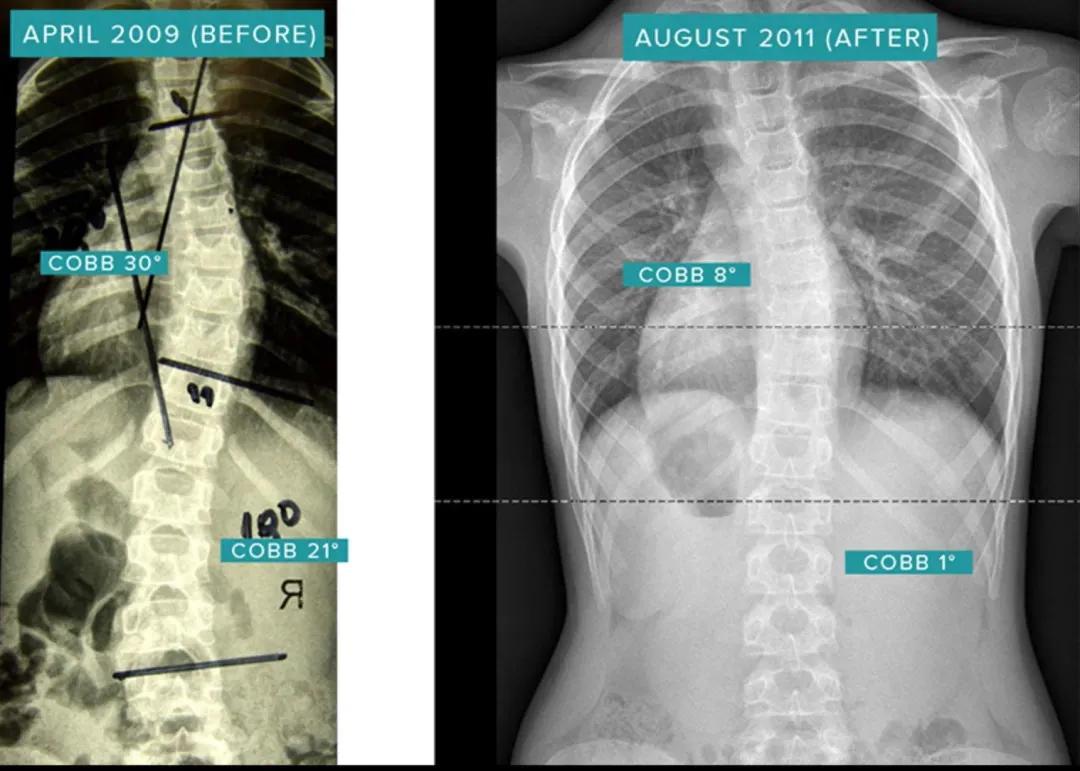

该患者在11岁时患有非常严重的脊柱侧弯,也因此在学校被人嘲笑,身体和心里都受到很深的上海,在接触sps疗法之前,患者接受了常规的康复治疗和,她的脊柱侧弯却从34°Cobb恶化到38°。后来,她开始接受SPS螺旋稳定治疗,使脊柱侧弯改善了6°Cobb,经过两年的治疗,体型问题彻底解决,她也重新找回来自信和快乐。

T12-L4 38°Cobb-> 32°Cobb(提高6°)